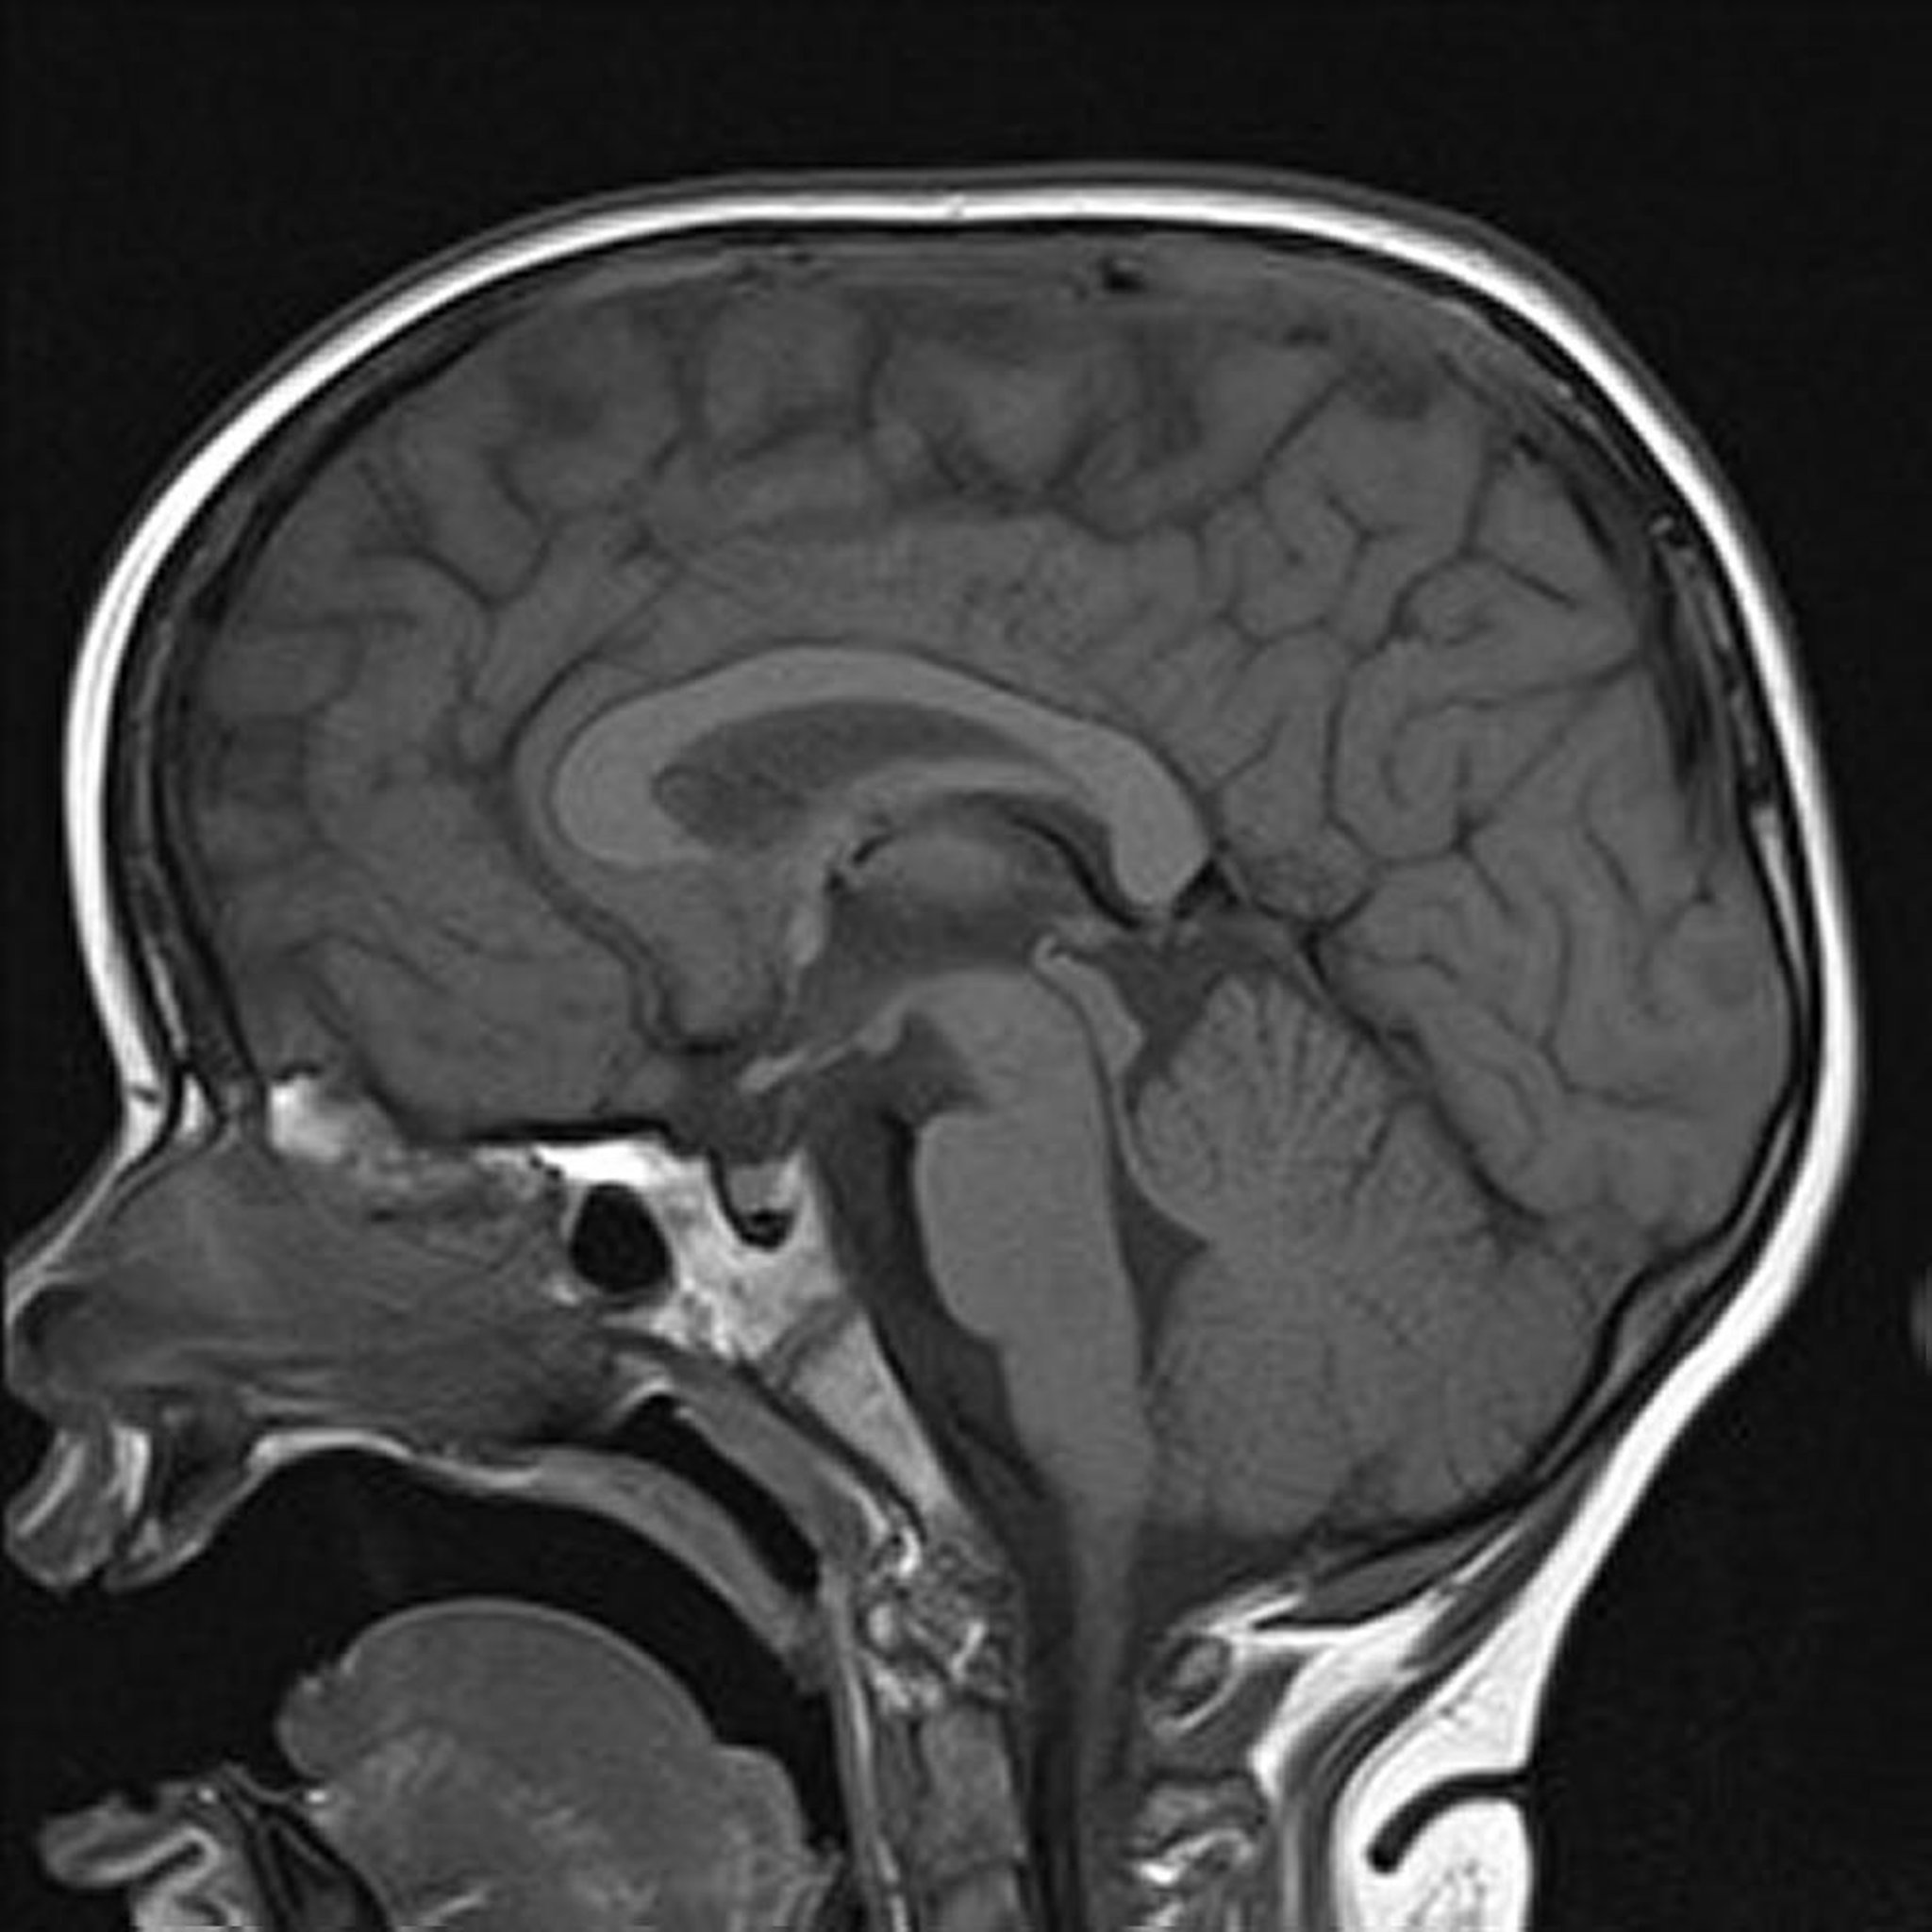

T1-взвешенная МРТ

Сагиттальное Т1-взвешенное изображение головного мозга показывает, что срединные структуры без изменений.

Image courtesy of Hakan Ilaslan, MD.